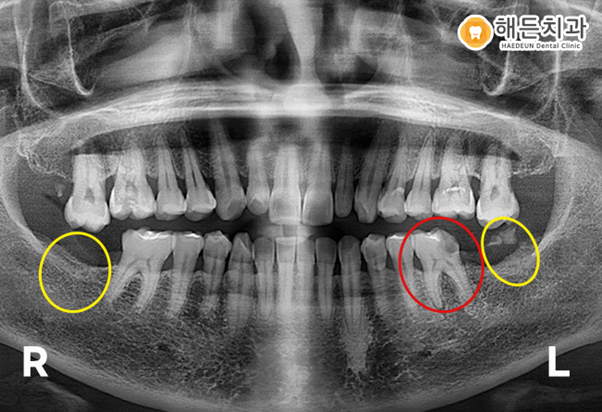

최후방 치아는 아주 일부분만 잔존하고 있는 상태이고, 더 이상 살릴 수 없는 경우라 발치 후 임플란트를 진행하기로 했습니다.

우선 환자분께서 가장 불편해 하신 왼쪽 아래 부위부터 상담을 도와드린 후, 전체적인 치료 계획을 수립하였습니다.

왼쪽 아래 최후방 구치와 더불어 오른쪽 아래 치아가 상실된 부위에도 임플란트를 진행하기로 했습니다.

그런데 파란색 동그라미의 위의 양쪽 최후방 어금니들을 보시면 치아가 밑으로 쳐져 내려와

옆에 치아들과 높이가 다른 것을 보실 수 있습니다.

맞물리는 치아가 상실된 후 오랫동안 방치한 경우, 치아들이 솟구치거나 내려 앉게 되는 정출이 발생하게 됩니다.